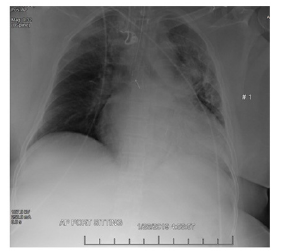

Electrocardiogram revealed possible left atrial enlargement and left ventricular hypertrophy, indicative of progressive left ventricular failure. Her electrocardiogram also showed anterolateral T-wave inversion (Figure 1). On telemetry, she had a normal sinus rhythm with a ventricular rate of 69. Transthoracic echocardiography revealed an estimated left ventricular ejection fraction of 25%. Additional findings include grade III diastolic dysfunction with elevated left atrial pressure, severe left atrial enlargement with severely abnormal left atrial ventricular index, severe right ventricular enlargement with normal function, right ventricular base measuring 5.6 cm, severely enlarged right atrium, severe mitral regurgitation, mitral regurgitation grade severity of 0.5 cm2, moderate to severe tricuspid regurgitation, and her inferior vena cava barely collapsed during inspiration suggesting elevated right atrial and ventricular end-diastolic pressures (Figure 2) Chest x-ray (Figure 3) revealed a nonspecific right infrahilar opacity suggestive of atelectasis or an infiltrative process, in addition to mild-to-moderate cardiomegaly.